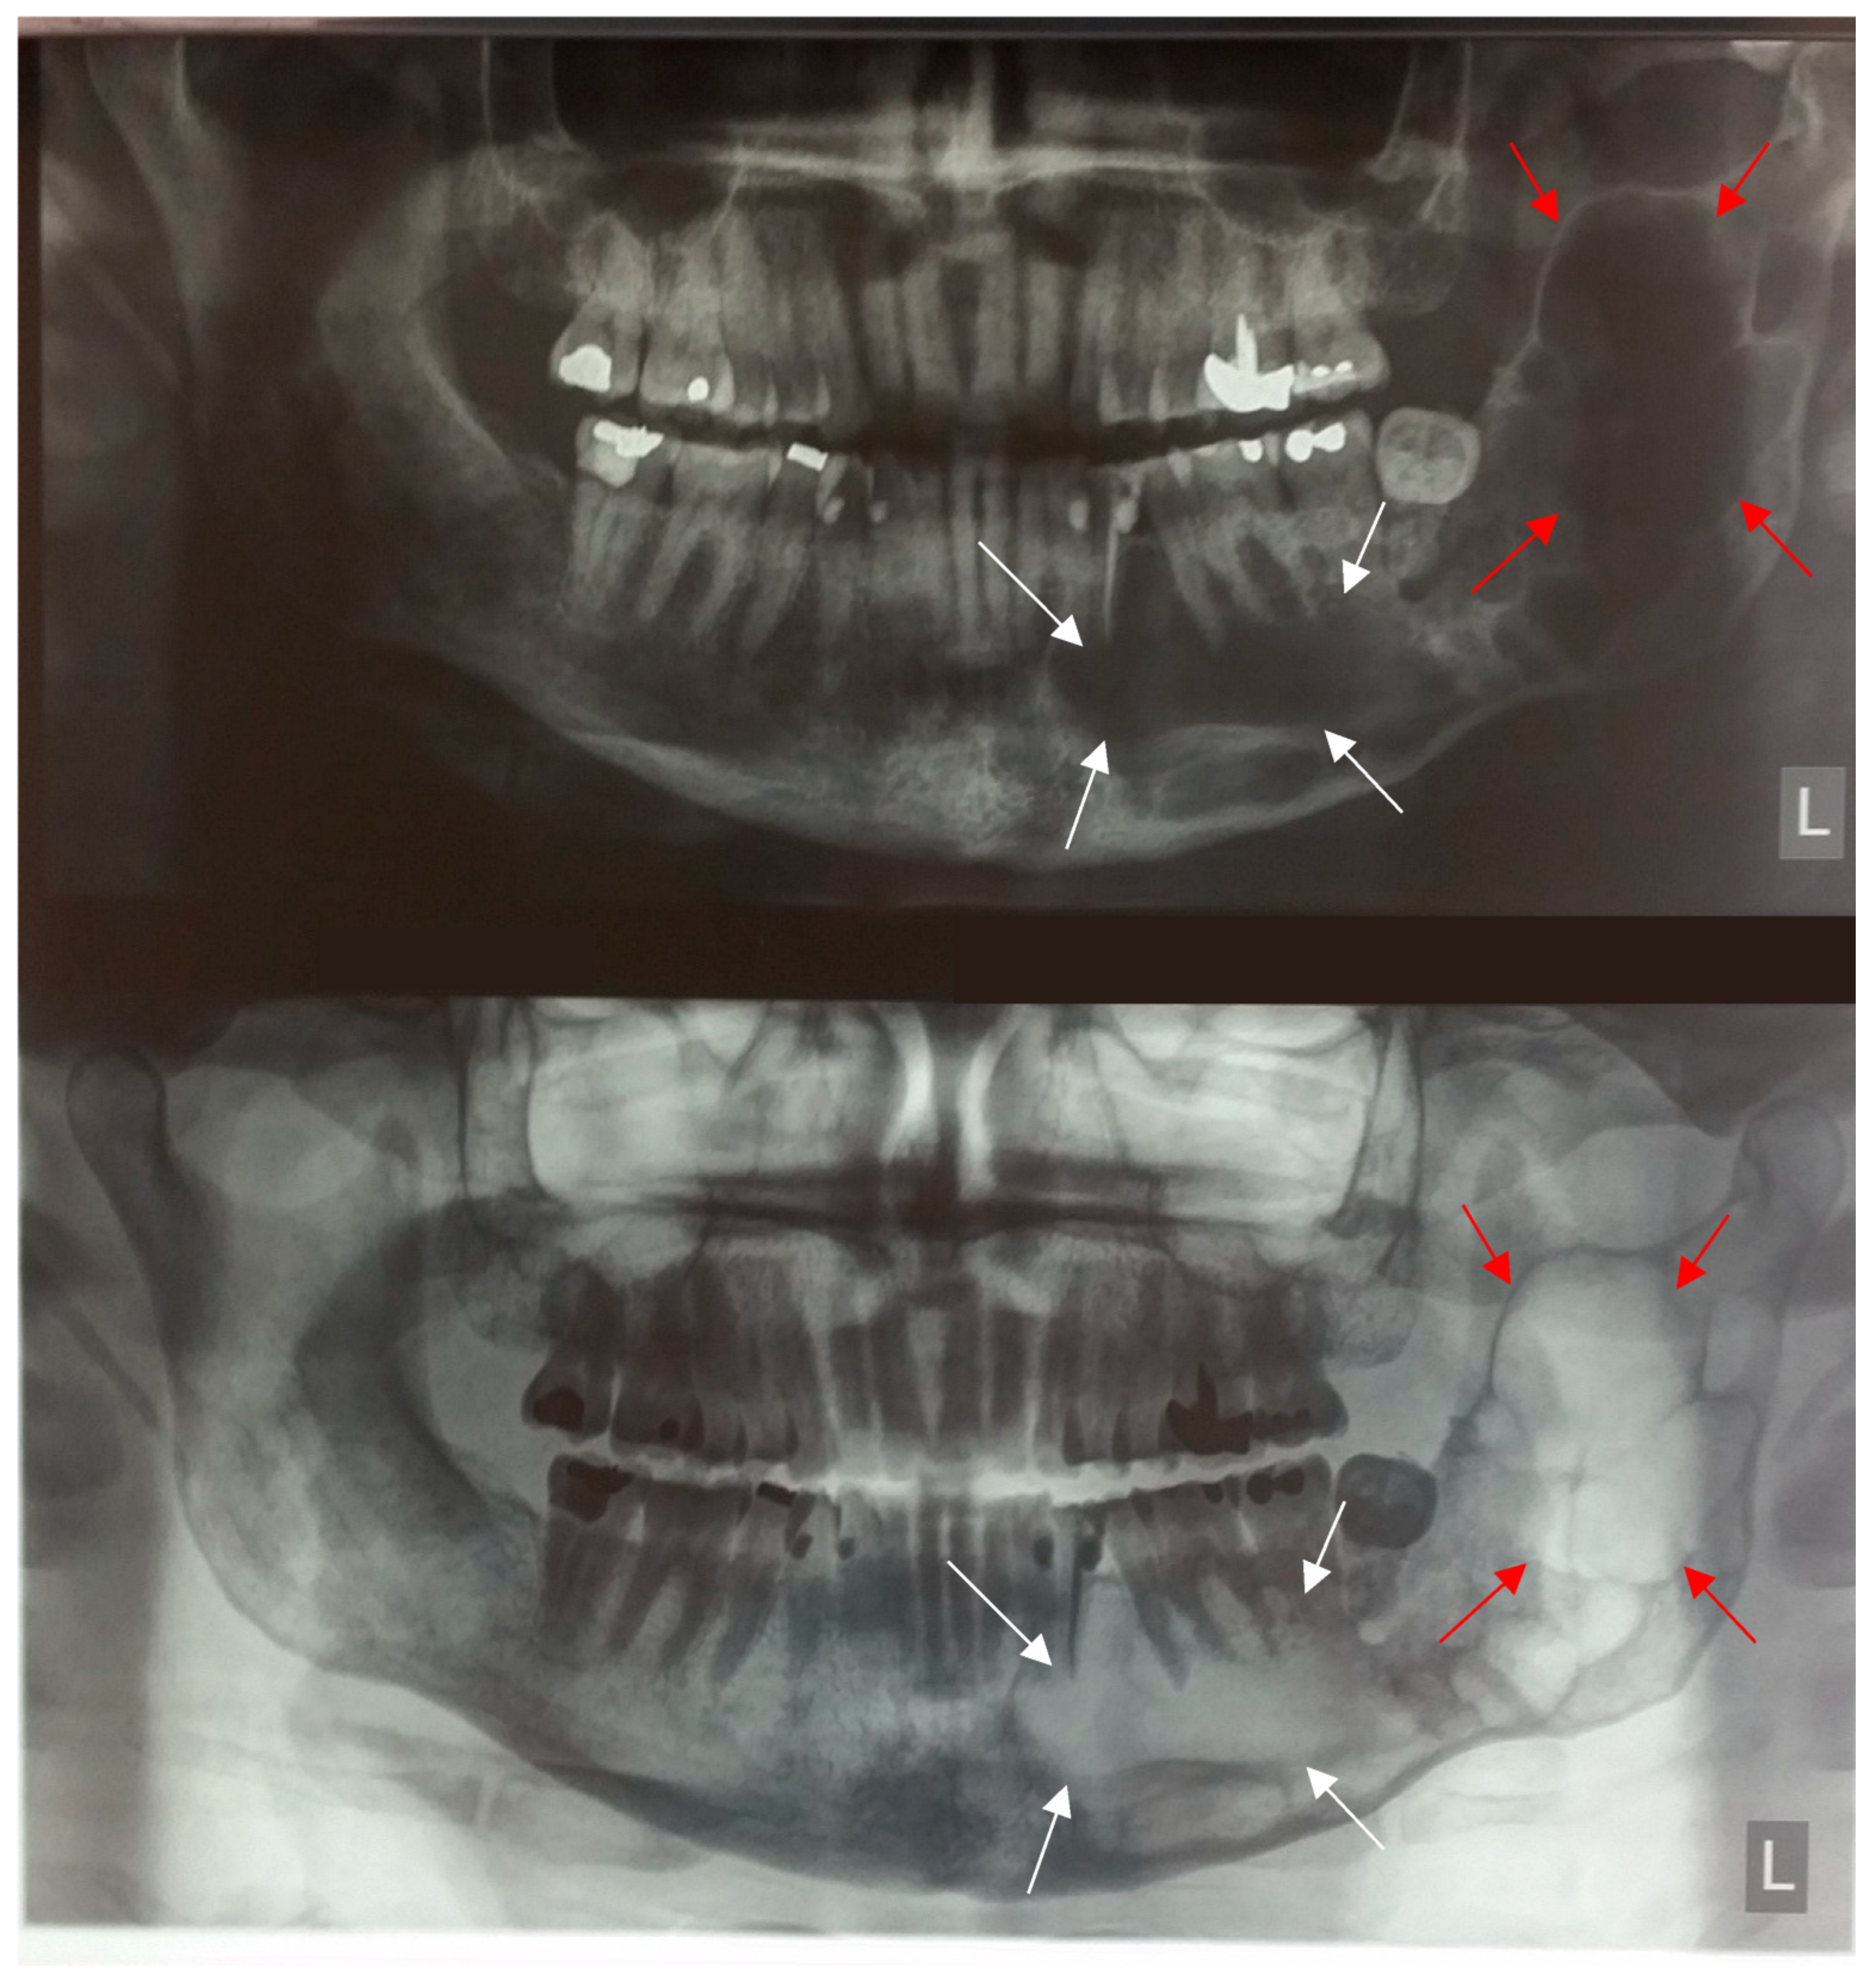

- Radiographic signs in maxilla e mandibular arches

- Focal disease—characterized by irreversible lesions such as osteonecrosis and osteosclerosis;

- Local disease—characterized by reversible abnormalities adjacent to the large medullae, such as cortical thinning and bone defects;

- Generalized osteopenia [88].